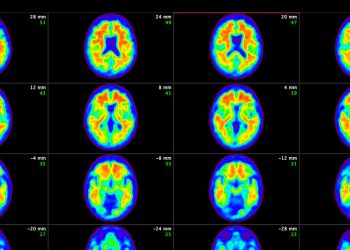

Deneysel bir ilaç olan donanemab ile yapılan bir deneme, hafızanın ve düşüncenin kötüleşmesini biraz yavaşlattığını ve daha erken evrelerde ve ...